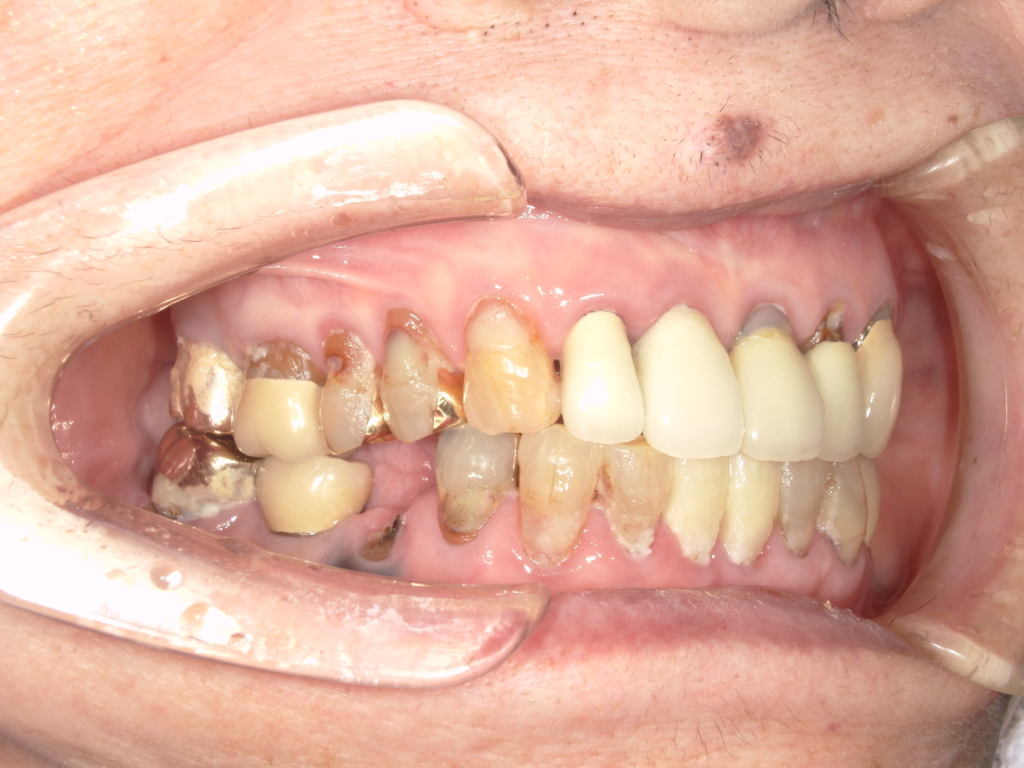

Y様インプラント実例 #44

左の上下の奥歯をインプラントで治療しています。

左下の奥歯は歯を抜くのと同時にインプラントの埋め込みを行っています。

被せものは上下、セラミックスで作っています。

治療前

治療後